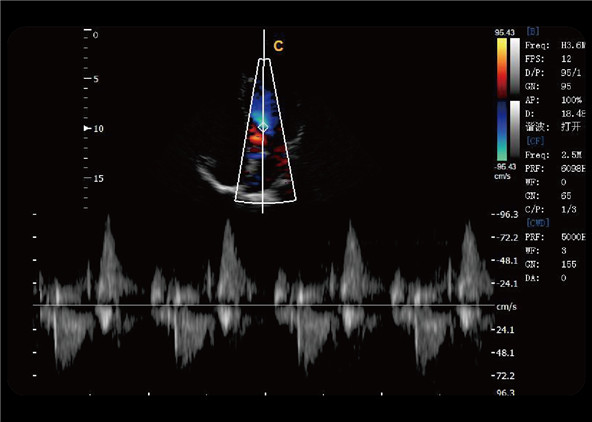

Detect blood flow with high velocity and help doctors diagnose with more clinical information.

Triplex combines B, color, with PW to help the user make diagnosis more conveniently and more accurately, help to improve the efficiency